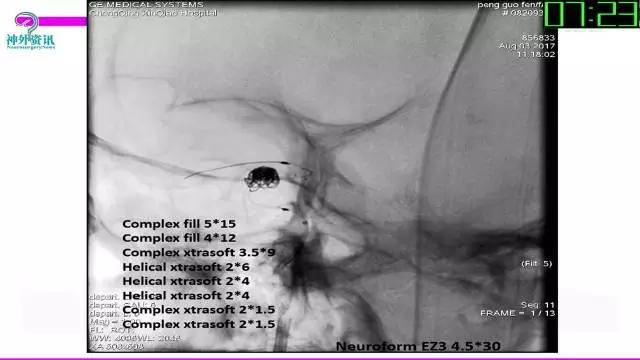

今天为大家分享的是“强生医疗CNV-神经介入专栏”第三十六期,由重庆第三军医大学附属新桥医院神经外科刘俊带来的“Galaxy弹簧圈在不规则动脉瘤中的临床应用”精彩讲课视频及PPT,欢迎观看。文章仅代表作者个人观点,如有不同见解,欢迎同道斧正!